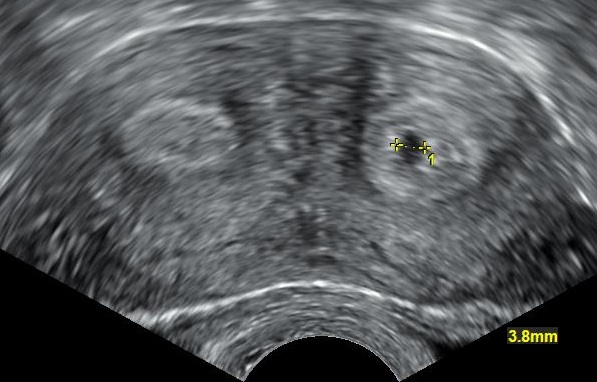

쌍각 자궁은 일반적으로 2D 또는 3D 부인과 초음파, 자궁난관조영술, 자기 공명 영상(MRI)을 사용하여 자궁을 영상화하여 진단한다. 영상에서 쌍각 자궁은 각 사이의 각도(각간 각도)와 기저부 열구 깊이를 측정하여 중격 자궁과 구별할 수 있다. 중격 자궁은 각간 각도가 75도 미만, 쌍각 자궁은 105도 이상이다. 1cm 이상의 기저부 열구는 쌍각 자궁을 나타낸다.[2]